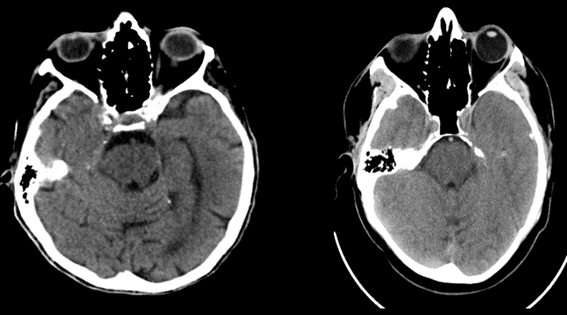

Encontramos como primer error el volumen parcial dado por estructuras vecinas, es frecuente con las estructuras óseas

Los lóbulos temporales y fosa posterior son afectados por artefactos de endurecimiento del rayo y se aprecian como zonas de hipodensidad irregular y no debe confundirse con gliomas. Se diferencian por la falta de masa.

Fig. 10.

Fig. 9.